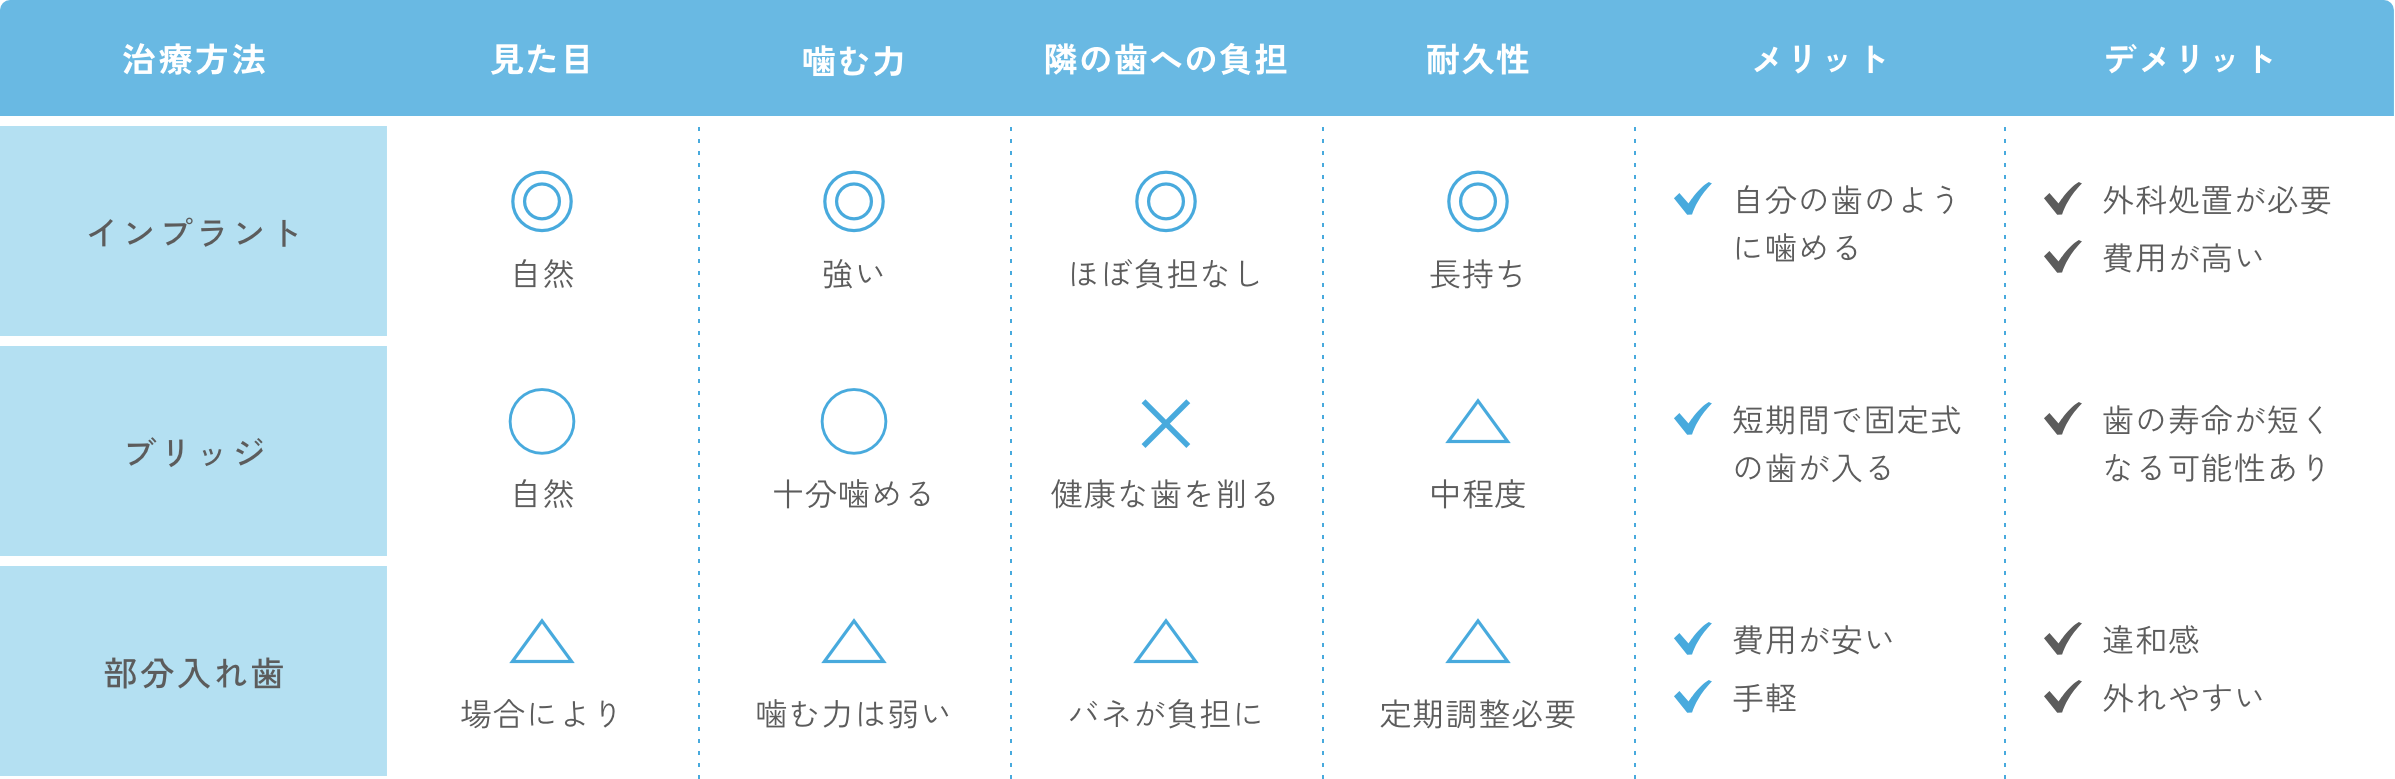

歯を失うと、「噛みにくい」「見た目が気になる」「隣の歯に負担がかかる」など、さまざまな問題が生じます。インプラント治療は、失った歯の機能や見た目を自然に回復させる治療で、自分の歯のような噛みごこちが得られることが最大の特徴です。

インプラントは、歯を失った部分の顎の骨に「チタン製の人工歯根」を埋め込み、その上に人工歯(セラミックの歯)を装着して歯の機能を回復する治療です。